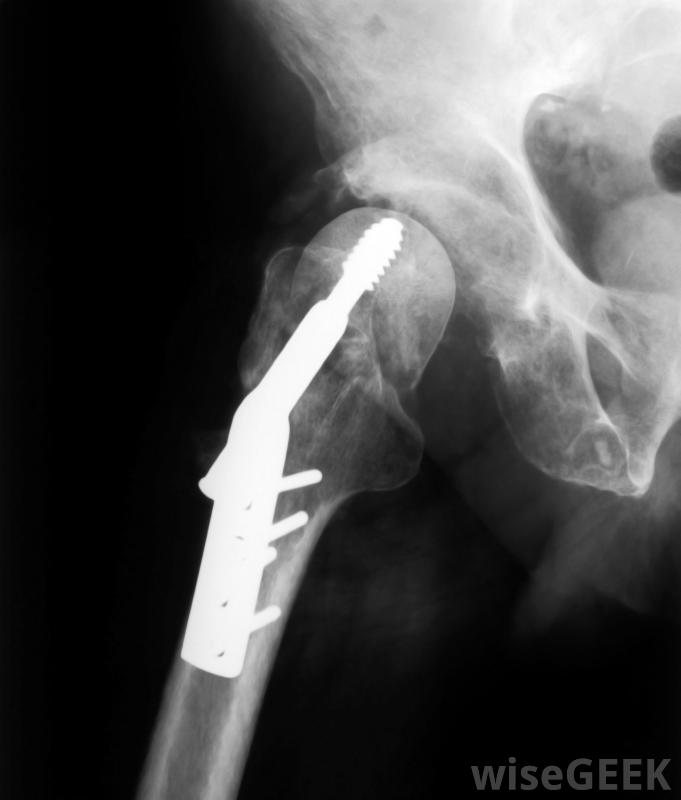

钛合金可用于骨折或其他损伤后重建骨骼或关节。钛因其强度高、重量轻而常被认为是一种神奇的金属,其强度与钢差不多钛的强度是铝的两倍,钛比钢轻45%,比铝重60%它还具有与人体无反应性的优点,是医疗植入物的理想选择,例如固定骨折的销钉。但是,它的高成本限制了它的使用。钛在地壳中相对常见,其含量约为0.57%(第九种最常见的元素),但从其矿石中提取出来——金红石(TiO2)、钛铁矿(FeTiO3)和榍石(CaTiSiO5)等矿物价格昂贵,这是由于需要较高的热量输入。元素钛在1910年才首次以纯形式分离出来,当Matthew A.Hunter在800°C(1472°F)下用钠加热TiCl4时,共有38种常见的钛合金,但典型的混合物是90%的钛,6%的铝,和4%的钒。这种混合物被称为5级。有1到38级的钛,其中38级是最新发明的。这些等级并不表示强度或任何东西,它们只是用来方便参考,尽管早期的等级是最早生产的。5级钛也被称为钛6AL-4V,它被认为适合军事用途。这种钛合金在高达400°C(752°F)的温度下稳定应用,典型的应用是在飞机涡轮中,涡轮旋转非常快,变得非常热。此外,还可以看到钛合金广泛应用于军事硬件,在保时捷(Porsche)和法拉利(Ferrari)等高端汽车的连杆中可以找到钛合金。这些金属的存在是导致这些汽车如此昂贵的原因之一,但同时也是可靠和能够高速行驶的原因之一。高级产品中类似的高端材料是碳纤维

钛合金可用于医疗植入物。